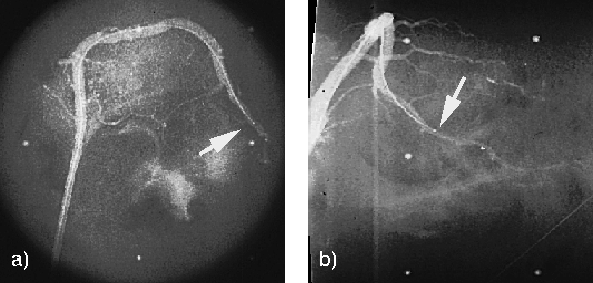

Angiograms of Cadaveric Pig RCA with IVUS Catheter